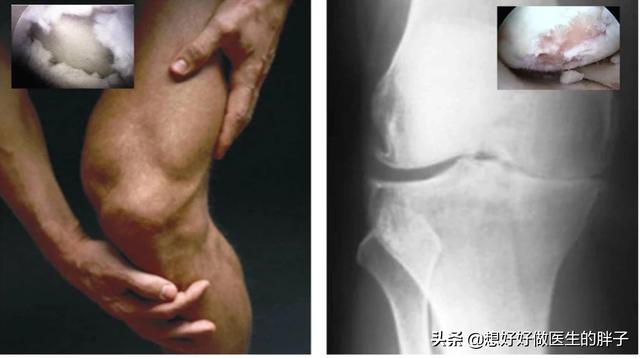

到了关节软骨磨损的晚期,很可能关节内负重区的软骨已经被磨得消失殆尽了。所以患者的关节往往会出现明显的间隙狭窄和大量的骨赘形成,此时的患者,严重的关节屈伸角度也会有明显的受限,而且疼痛会对患者的整个生活造成非常大的困扰,有些比较重的患者甚至会出现休息的时候关节也疼痛,而且在夜间休息的时候能疼醒,此时以前的一些治疗方法就很难帮助患者解决问题了,进行关节置换或者是部分关节置换,是解决患者问题的最佳措施(康复锻炼一样要做)。